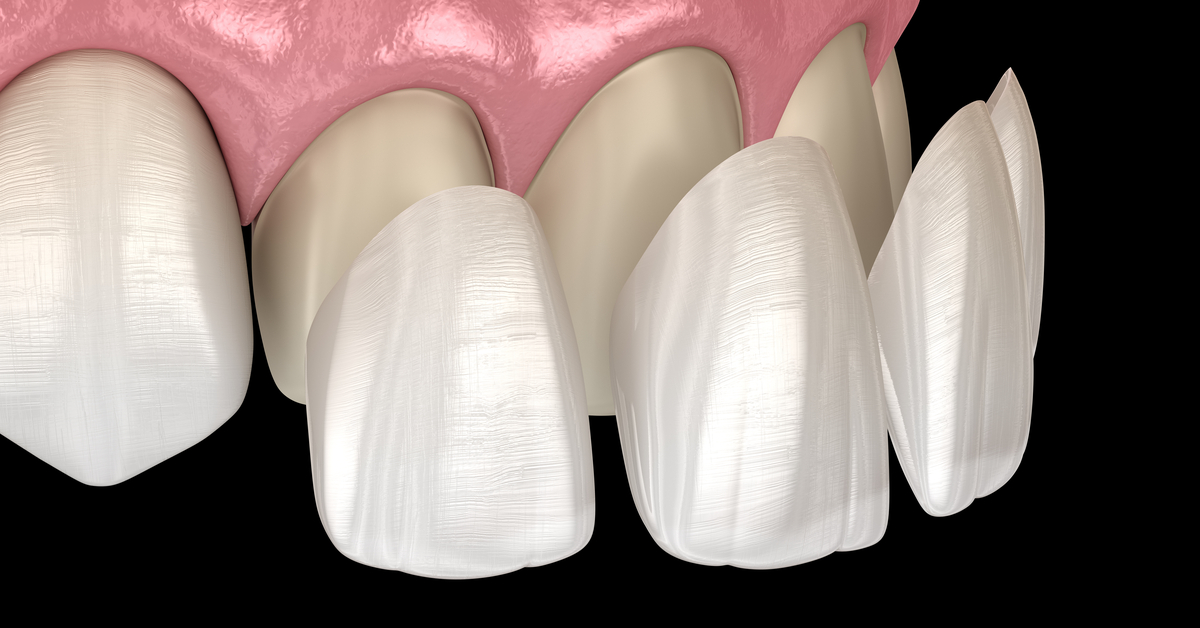

الفينير

الفينير هو قشور تجميلية رقيقة تُثبت على سطح الأسنان، ويُعد الحل الأمثل في حالات التصبغات العميقة، حيث:

- يغطي اللون الداكن بالكامل

- يعطي لونًا موحدًا وطبيعيًا

- يدوم لسنوات طويلة مع العناية الجيدة